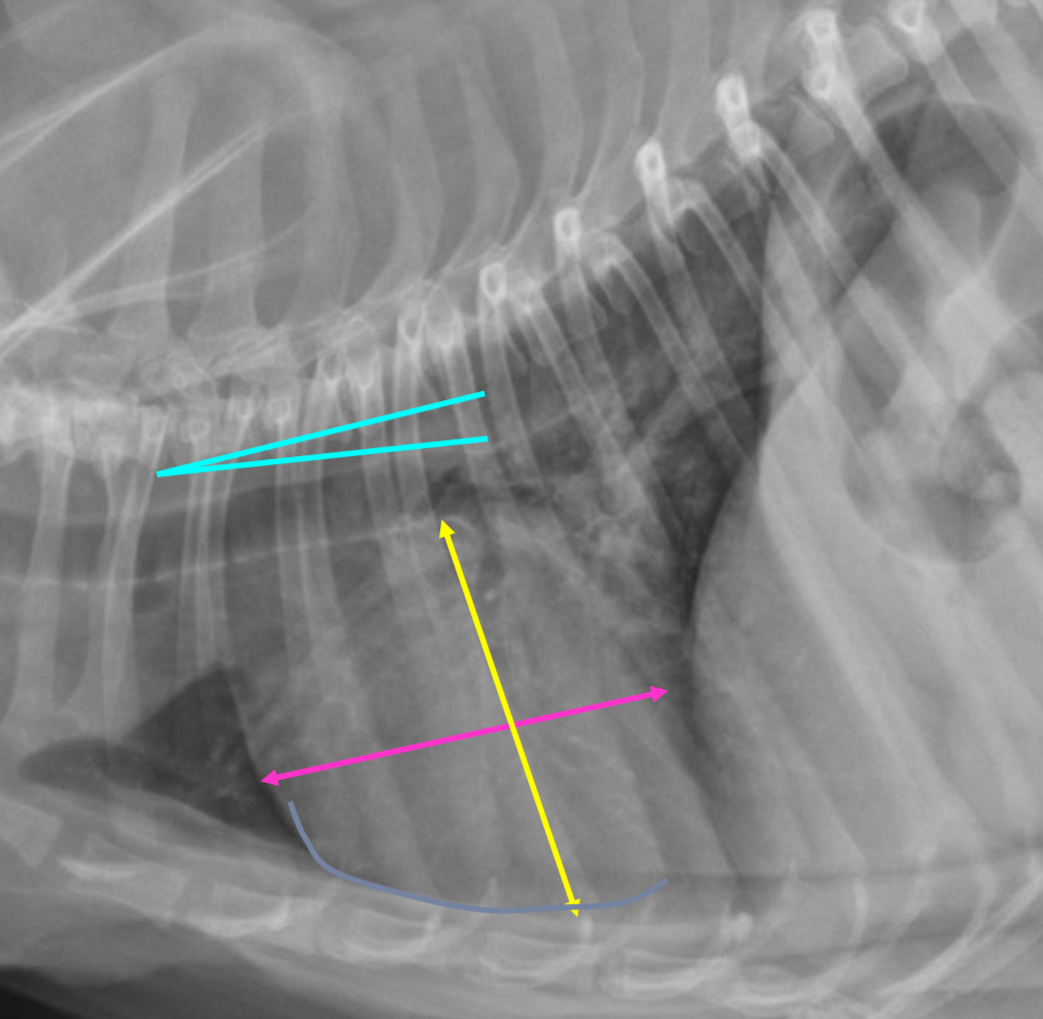

What part of the heart is enlarged

LAE

3 features of LAE on DV

-double opacity sign

-separation of main stem bronchi

-LA bulge at 2:30-3 o’clock